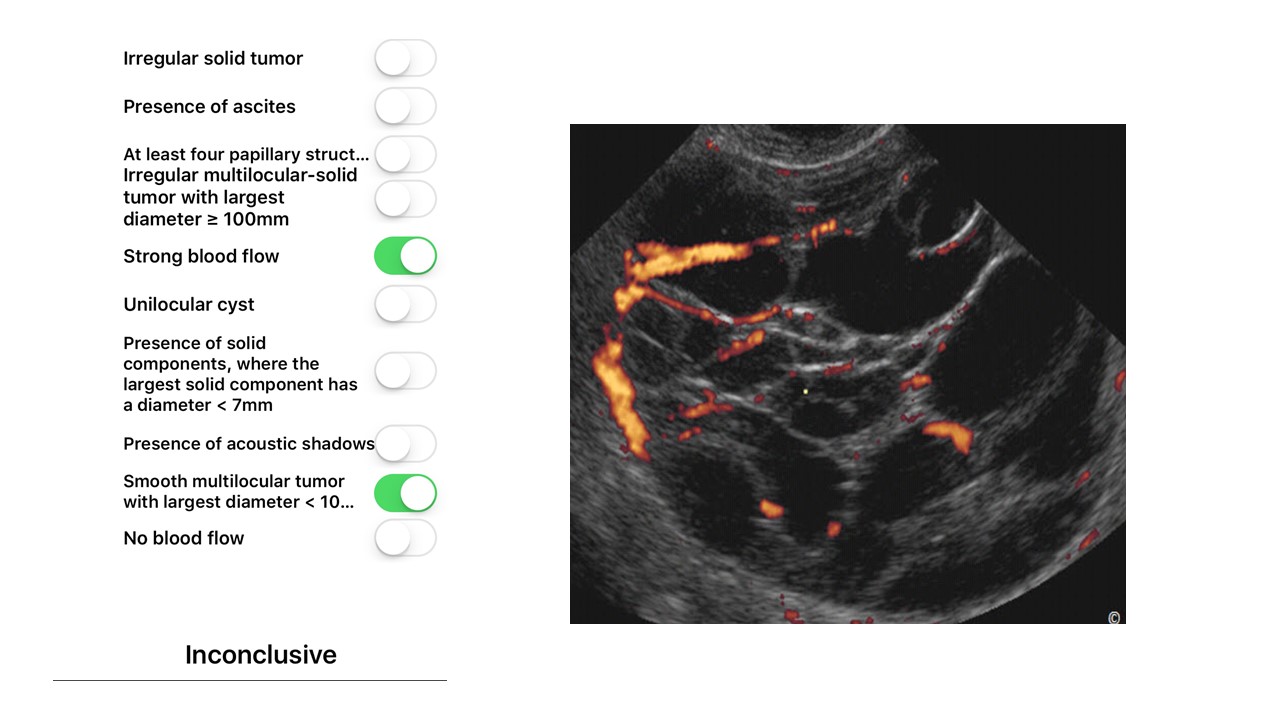

Tiếp cận chẩn đoán và phân tầng xử trí khối u buồng trứng theo IOTA-ORADS

Từ khóa: Tiếp cận chẩn đoán và phân tầng xử trí khối u buồng trứng theo IOTA-ORADS